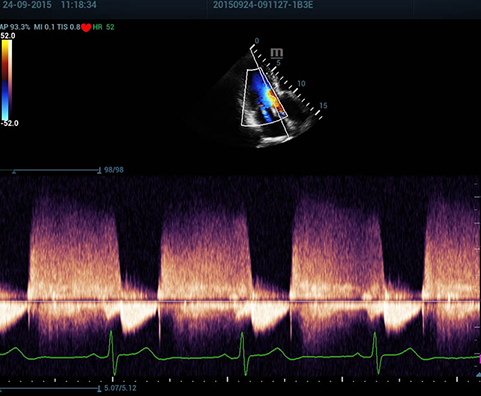

Resona 7 — качество изображений уровня премиум и новые клинические возможности. Система V Flow теперь способна не только оценивать гемодинамические показатели с частотой 600 кадров/сек, но также обеспечить интеллектуальное получение из 3D данных наиболее важных проекций для диагностики ЦНС плода.

Обеспечивая качество изображения уровня премиум, Resona 7 также повышает клинические возможности исследования при помощи революционной системы V Flow, предназначенной для оценки гемодинамических показателей сосудов; обеспечивает интеллектуальное получение из 3D данных наиболее важных проекций для диагностики ЦНС плода. Сочетая в себе интуитивно понятное сенсорное управление с распознаванием жестов и все важные клинические характеристики, передовая система Resona 7 настоящая новая волна в сфере ультразвуковых инноваций.Благодаря перечисленным выше характеристикам, Resona 7 является доступным решением премиум-класса, которое удовлетворяет высоким требованиям клинической точности и эффективной диагностики в условиях современной перегруженной больничной среды.

Echo Boost™ - режим улучшенной визуализации структур сердца

SP5-1U – секторный датчик для исследований брюшной полости, нейросонографии, а также детской и взрослой кардиологии. Датчик поддерживает THI, Smart3D, iScape, TDI, совмещенная картинка и контрастное изображение, а также биопсию и работает на всех режимах, включая CWD

Недостаточность аортального клапана